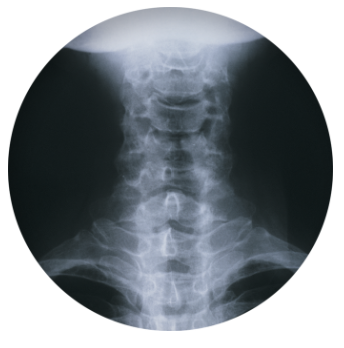

목 디스크는 목의 디스크(뼈 사이의 쿠션 역할을 하는 물질)가 손상되거나 파열되어 인접한 신경 및 조직에 압박을 주어 생기는 질환이다. 주로 긴 시간동안 고강도의 목 부담이나 부상 등이 원인이 되며, 목 아래쪽 통증, 근육약화, 두통, 어깨 및 팔에 통증, 미각 및 후각 상실 등의 증상이 나타난다. MRI 등의 영상진단을 통해 진단이 이루어지며, 보존적 치료와 수술적 치료가 가능하다. 초기 치료로는 안정 및 물리치료, 약물치료 등이 시행되고, 증상이 심한 경우 수술적 치료를 고려할 수 있다.

목 디스크는 경추부 디스크가 손상되어 디스크의 누출이나 폭발적인 파열 등의 문제가 발생하는 질환입니다. 이러한 문제로 인해 디스크가 인접한 신경에 압력을 가하게 되어, 강한 통증, 근육 경련, 저림 등의 증상이 나타납니다. 이 중에서 대표적인 증상은 목의 통증과 뻣뻣함, 두통, 어깨와 팔의 통증 및 저림 등이 있습니다. 또한, 목 디스크는 목을 움직일 때 통증이 증가하는 것이 특징입니다. 이러한 증상들은 주로 목 디스크가 경추부에서 발생할 때 나타나며, 경추부 디스크가 척추신경을 압박할 경우, 근육의 경련으로 인해 근육 긴장도 높아지는 경우가 많습니다.

또한, 목 디스크가 척추 신경근의 인대에 압박을 가할 때, 머리와 어깨가 뒤틀리는 증상이 나타날 수 있으며, 심한 경우에는 근육이 압박에 대한 보호 반사로 인해 경련이 발생하기도 합니다. 이 경우, 손가락이나 팔꿈치 같은 지점에서도 저림이 발생할 수 있으며, 목 디스크가 퇴행성 질환의 일종이기 때문에 증상은 서서히 나타나게 됩니다.

다만, 목 디스크 증상은 모든 환자에서 동일하지 않으며, 디스크의 위치, 크기, 손상 정도 등에 따라서 증상이 다르게 나타날 수 있습니다. 따라서, 정확한 진단과 치료가 필요합니다.